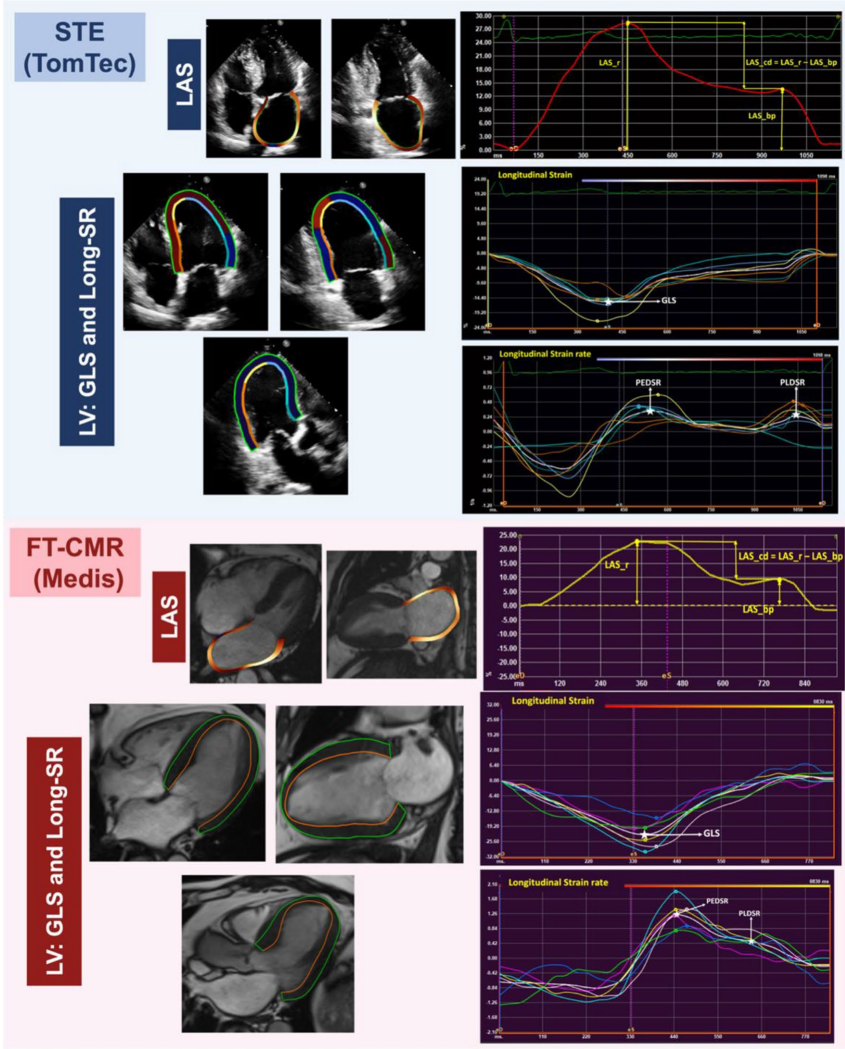

本研究针对心肌形变评估中不同影像学技术间一致性与可重复性数据缺乏的问题,由Aseel Alfuhied团队系统比较了经胸超声心动图(TTE)与心血管磁共振(CMR)对左心房应变(LAS)和左心室应变/应变率(LV S/SR)的测量差异。结果显示两种技术对LAS具有中等一致性(ICC=0.55-0.69),但对LV参数一致性较差(除PLDSR外ICC均<0.5),表明TTE与CMR不可互换使用。在10例2型糖尿病(T2D)患者的重复性测试中,CMR对LAS和LV应变率的重复性总体优于TTE。该研究为临床选择心肌形变评估方法提供了重要依据。